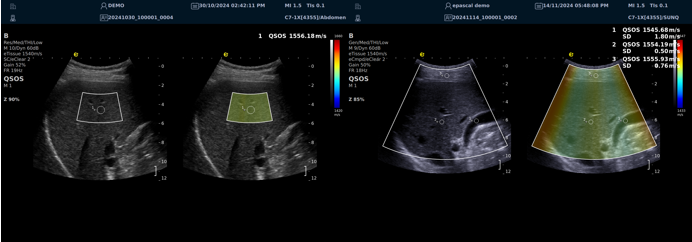

QSOS声速定量成像

测量原理

QSOS声速成像技术利用声波在组织中的传播速度差异性,计算不同位置的声速值,反映组织的物理特性。

成像过程

利用超声探头发射超声波脉冲,分析反射信号的时间延迟,确定声波传播路径和速度,构建声速分布图像。

图像显示

QSOS技术采用彩色编码显示声速图像,不同颜色代表不同声速值,便于医生识别病变部位和测量。

技术优势

?精准定量反映组织特性,成像更敏锐?彩色编码直观显示,轻松发现异常?捕捉声速差异,早期、微小病变更易察觉

肌骨领域的应用

?精准定位损伤部位?判断损伤严重程度?监测肌肉营养?评估肌少症?骨质疏松评估